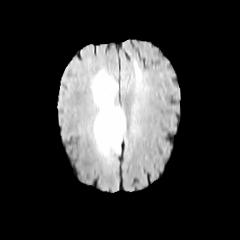

Glioma is a prevalent brain tumor that poses a significant health risk to individuals. Accurate segmentation of brain tumor is essential for clinical diagnosis and treatment. The Segment Anything Model(SAM), released by Meta AI, is a fundamental model in image segmentation and has excellent zero-sample generalization capabilities. Thus, it is interesting to apply SAM to the task of brain tumor segmentation. In this study, we evaluated the performance of SAM on brain tumor segmentation and found that without any model fine-tuning, there is still a gap between SAM and the current state-of-the-art(SOTA) model.